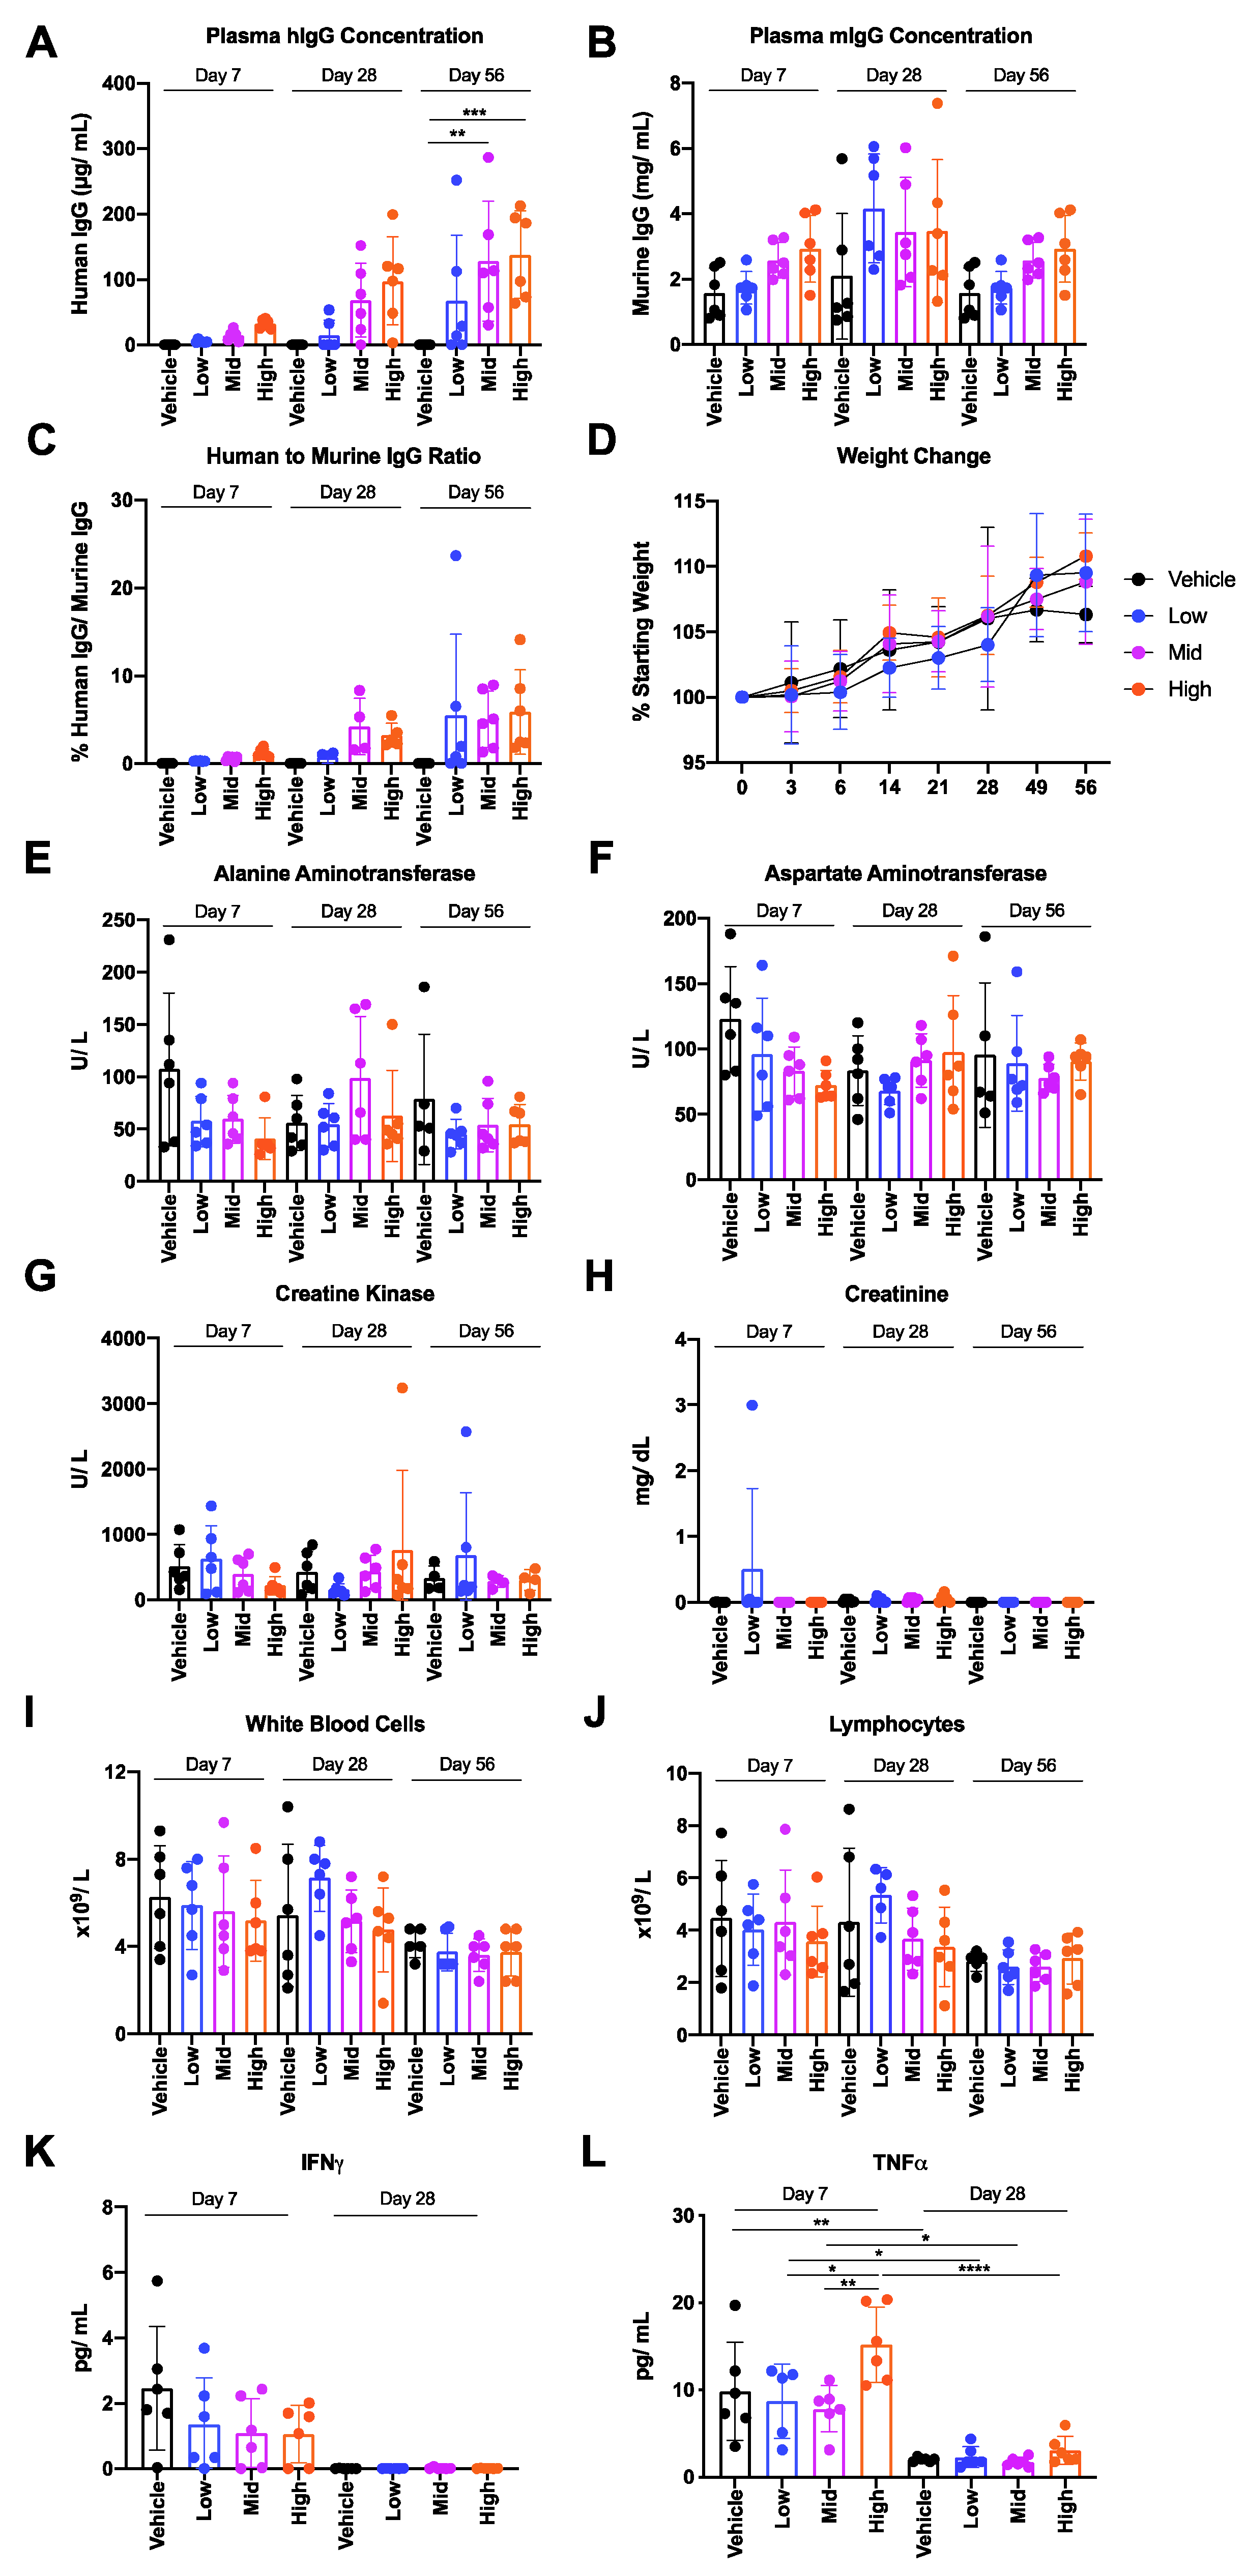

3.2. Safety and Tolerability of AAV6.2FF-31C2 in a Murine Model

3.3. Safety and Tolerability of AAV6.2FF-31C2 in a Pediatric Ovine (Sheep) Model